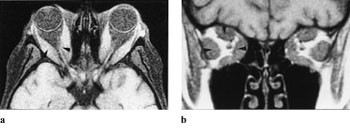

CT med koronalt og aksialt snitt er å foretrekke ved endokrin oftalmopati. Et karakteristisk CT-funn er en relativt symmetrisk forstørrelse, først og fremst av nedre og mediale rette øyemuskler. I 90 % av tilfellene kan det avdekkes patologiske forhold bilateralt, til tross for ensidige symptomer. Aksiale og koronale plan viser godt fordelingen og graden av muskelforstørrelse og forholdet til synsnerven ved orbital apex (8). Det er en relativ sparing av muskelsenen, mens det er særlig fortykket midtre og bakre del ved muskelbunten som er typisk og muliggjør differensiering fra myositt. Endokrin oftalmopati forekommer i 2 – 7 % av tilfellene av Graves sykdom, i aktiv fase med inflammasjon og lymfocyttinfiltrasjon i retrobulbært orbitalt vev, i utbrenningsfasen med fibroser. Et fokalt lavattenuerende område innenfor muskelbunten er et annet CT-funn som tyder på endokrin oftalmopati. Tidlig i forløpet finnes lymfocytisk infiltrasjon og fokal mukopolysakkaridavleiring, mens fettinfiltrasjon forekommer i den senere fasen. Andre hyppige funn ved Graves sykdom er ekspansjon av det orbitale fett, som presser orbitalseptum fremover og dermed strekker synsnerven.

Ved MR-undersøkelse med STIR-frekvens (fettsuppresjon) kan man grunnet økt vanninnhold påvise høysignalområder i aktiv fase i fortykkede muskler (fig 7 a, b). MR kan gi opplysning om muskelkontraktilitet ved repetisjon over flere minutter. Dette kan hjelpe til å oppdage subklinisk sykdom og demonstrerer det naturlige forløpet av sykdommen. Strabismeoperasjon bør utsettes til det ikke påvises noen aktivitet i sykdommen i en eller flere muskler, og botulinumtoksininjeksjon bør unngås hvis muskelen er klart fibrotisk og rigid. Immunsuppressiv behandling bør bare gis ved aktiv sykdom, når inflammasjon er påvist ved STIR-teknikk (9).

Lymfomer involverer oftest øvre del av orbita, inklusive øvre rette øyemuskel, og presser øyet nedover (fig 8 a, b). Det er svært vanskelig å differensiere røntgenologisk mellom lymfoid lesjon og lymfom i orbita, men der er også overlapping mellom de forskjellige typer histologisk. Karakteristisk er det, som også ved myositt, at muskelsenen er affisert. Både på MR og CT sees lymfomene som homogene, velavgrensede strukturer.